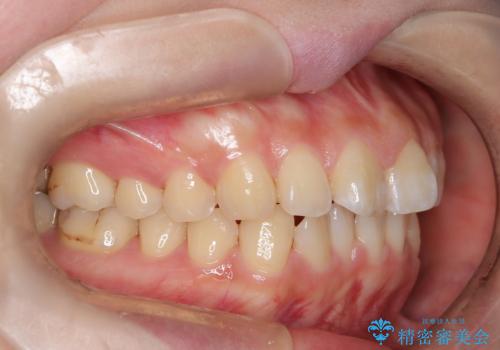

- 口元の突出感、歯のがたつきを主訴に来院された患者様です。非抜歯にて口元を下げるような治療計画を立案しました。非常に治療に対して真面目で協力的な患者様で、一緒に理想形を相談しながら治療を進めました。矯正前には、虫歯治療や親知らず抜歯を行っています。噛みしめ癖が強く、終盤は奥歯の噛み合わせのためにゴム掛けにご協力いただきました。